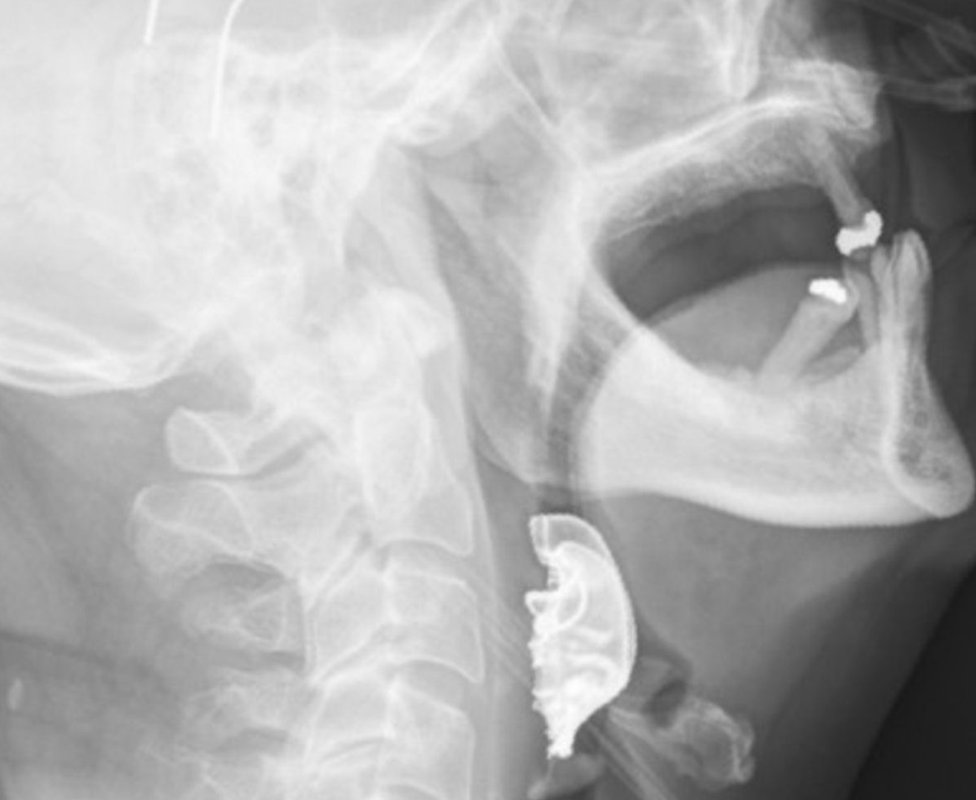

Kada se muškarac dva dana kasnije ponovo javio kod lekara, medicinsko osoblje pregledalo je grlo i glasne žice - i pronašlo polukružni predmet koji leži preko njih.

On je lekarima rekao da je za vreme operacije u bolnici izgubio protezu.